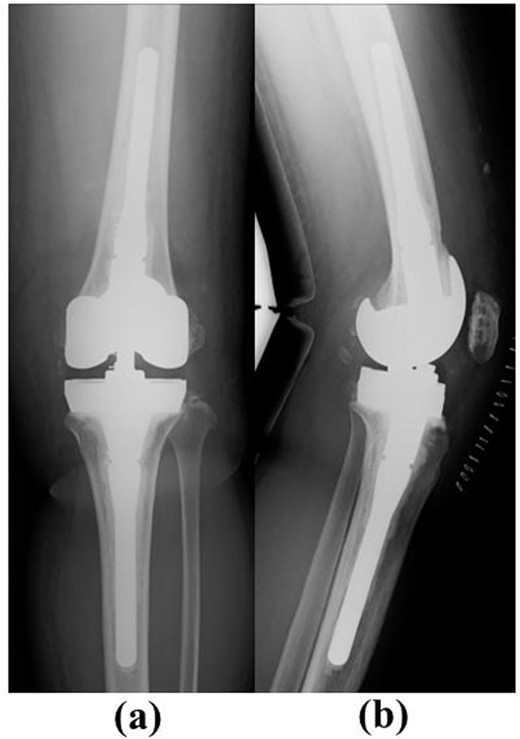

The NexGen Legacy Constrained Condylar Knee (LCCK) (Zimmer Biomet) with stem extension on both the femoral and tibial sides was chosen. Full block augmentation (10 mm) was used on the tibial side (Fig. 7).

Post-operative plain radiographs after revision total knee arthroplasty. (a) Anteroposterior view and (b) lateral view. The NexGen LCCK (Zimmer Biomet, Warsaw, IN, USA) with stem extension on both the femoral and tibial sides was chosen. Full block augmentation (10 mm) was used on the tibial side.

At 1 year after revision surgery, active ROM improved from 0 to 120°. The 2011 Knee Society Score symptom, patient satisfaction, patient expectation and daily activity subscores [9] were 24, 30, 9 and 92, respectively, compared with 5, 10, 15 and 55 before revision surgery.